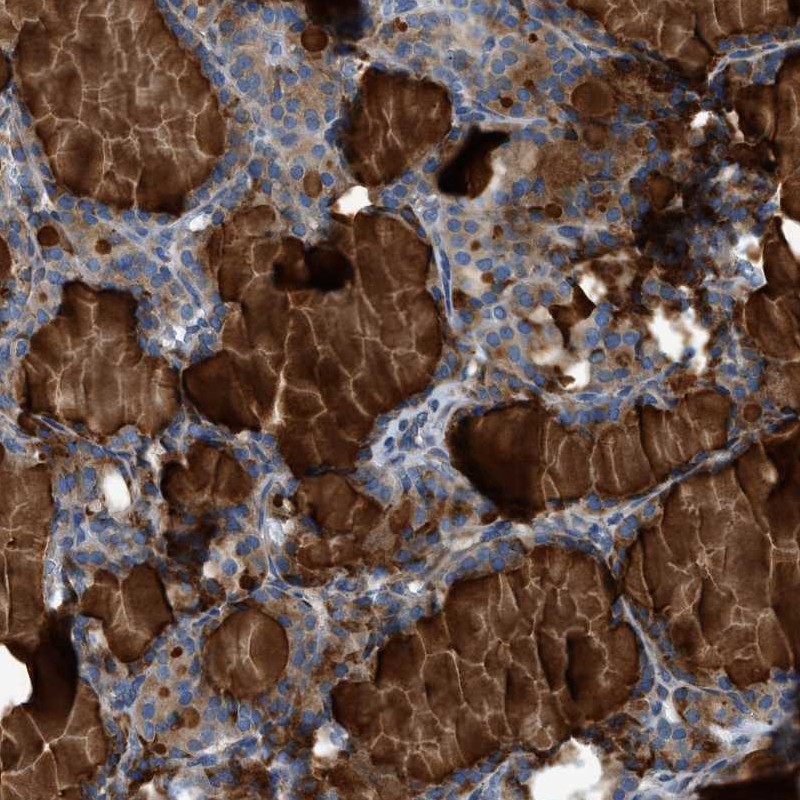

Immunohistochemical staining of human thyroid gland shows cytoplasmic positivity in glandular cells.